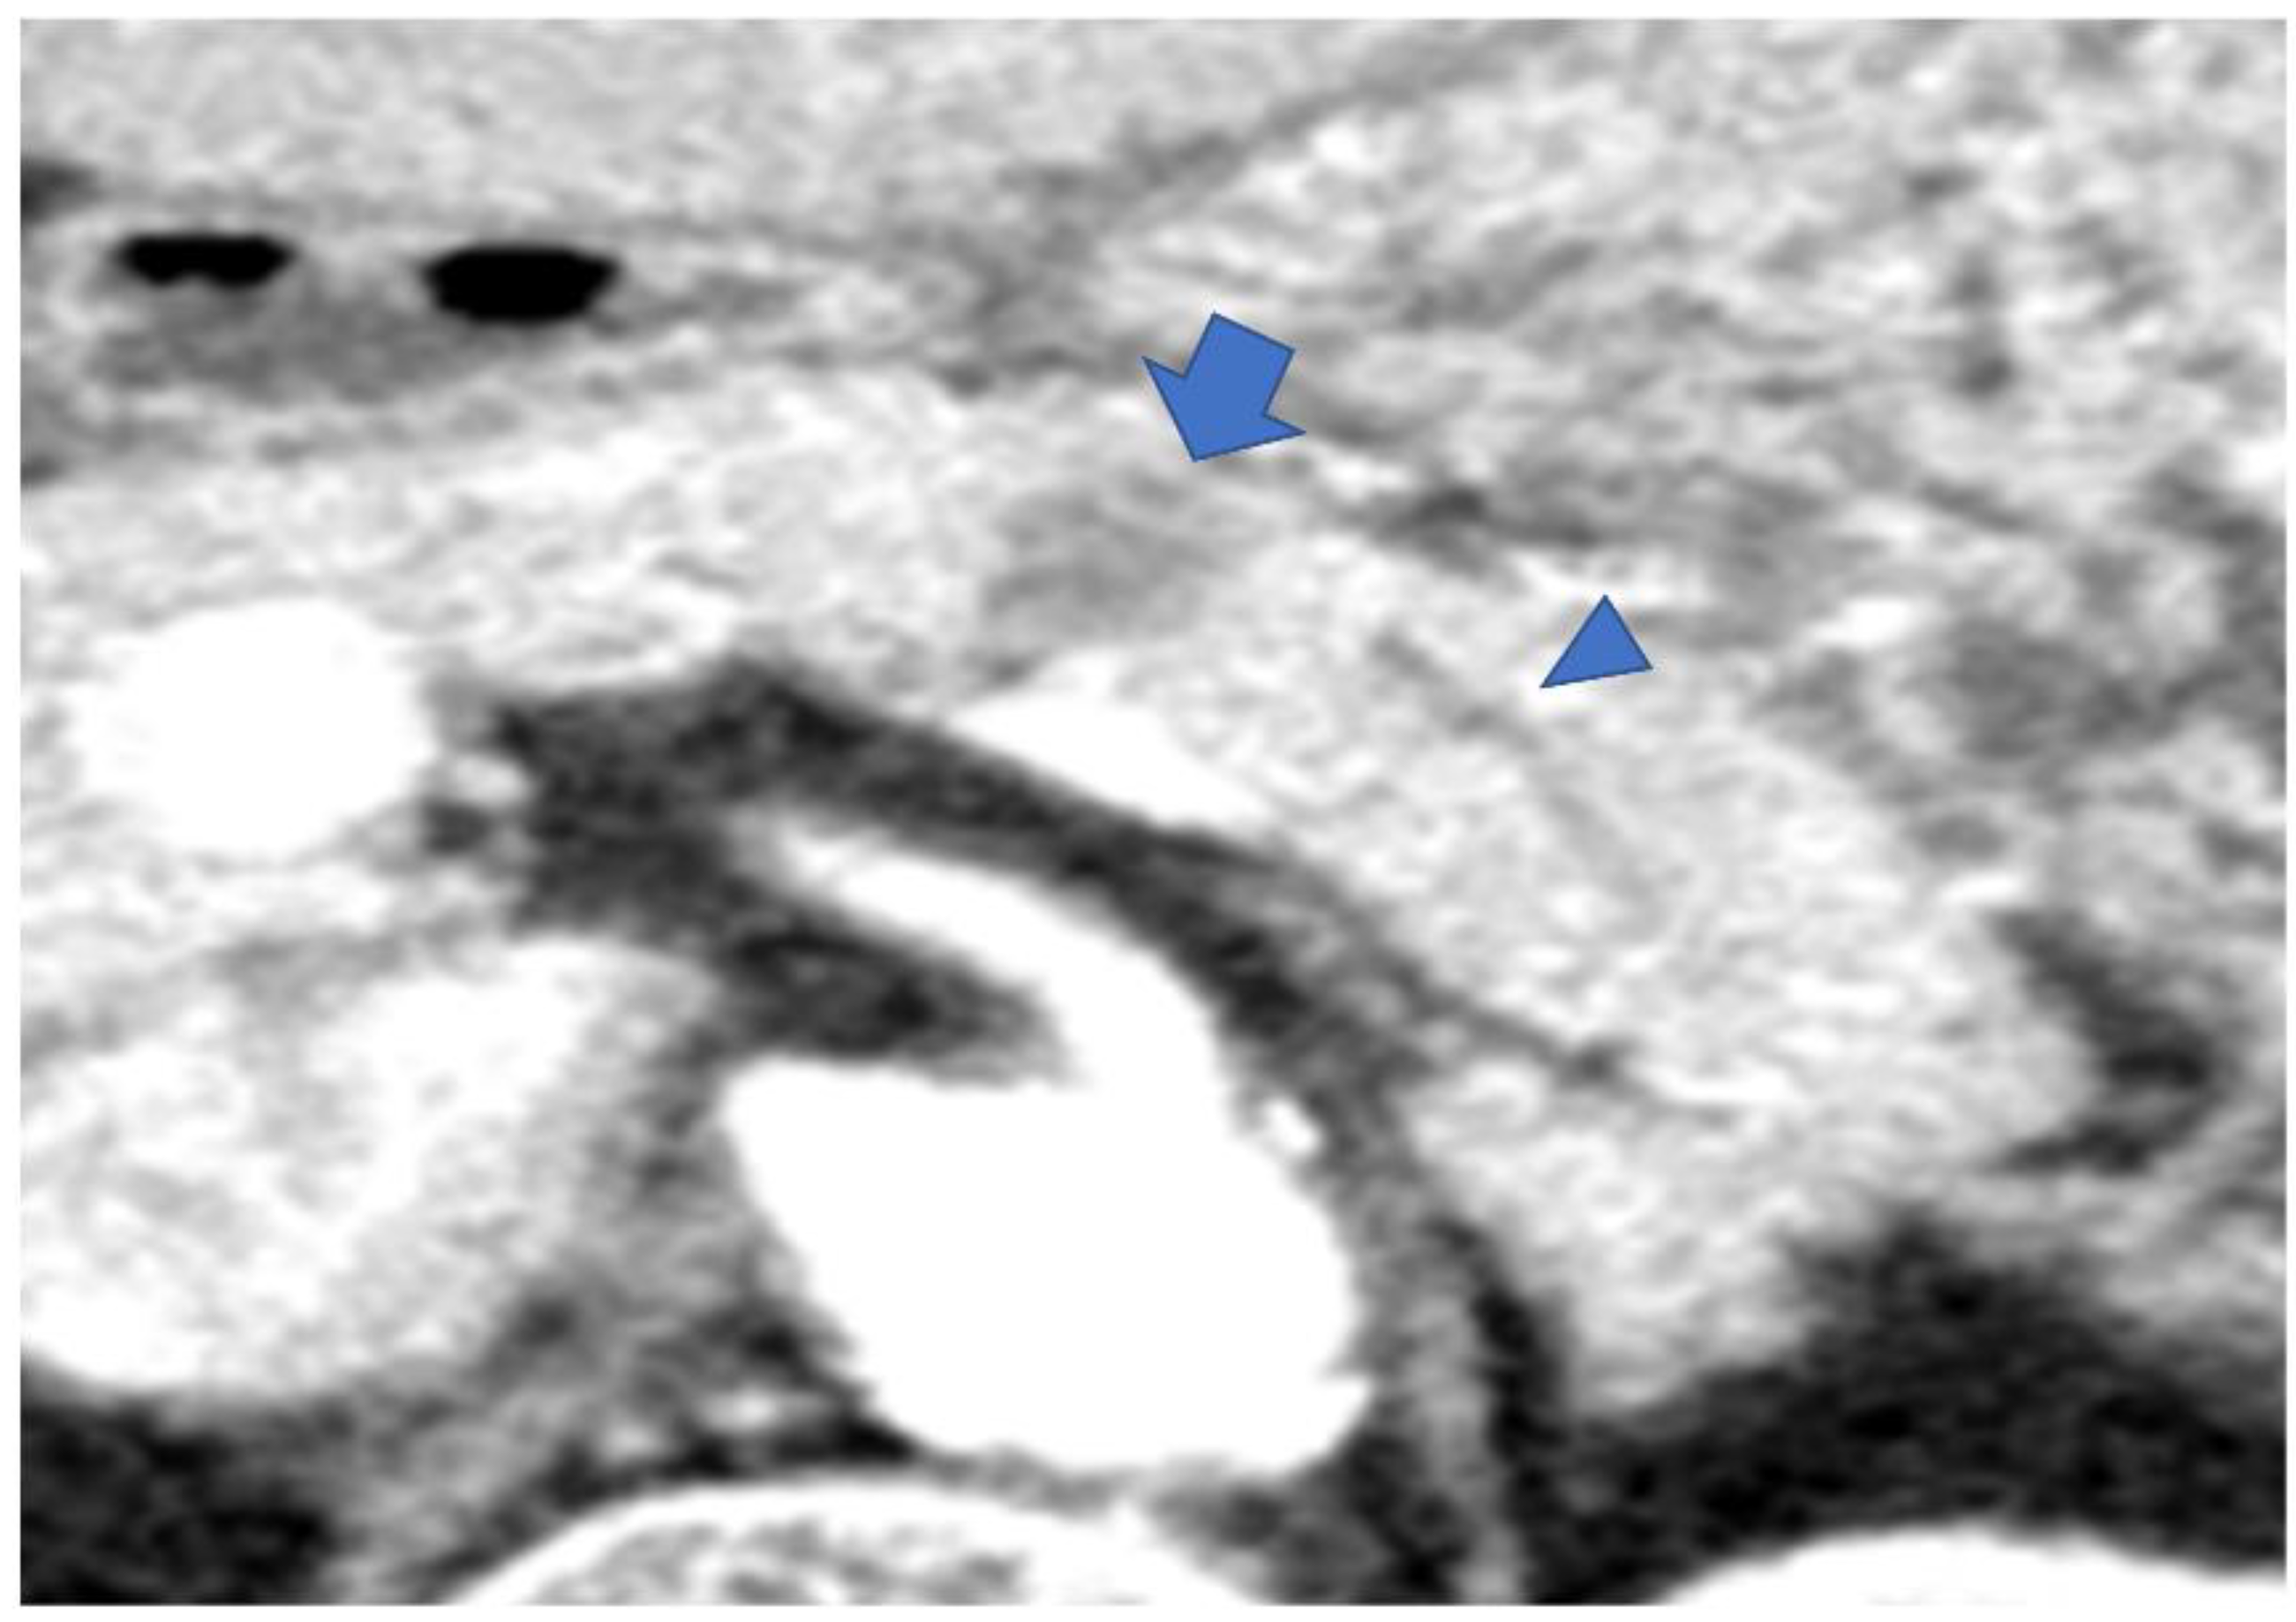

3.3. Imaging Findings